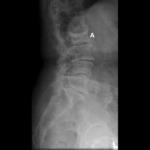

ხერხემლის რენტგენი: "winking owl" (ბუ, რომელიც თვალს გვიკრავს) ნიშანი (ხერხემლის ასიმეტრია, რაც გამოწვეულია მალის რკალის ფეხის დესტრუქციით

ექიმ Dr D. Park-ის საკუთრება; გამოყენებულია ნებართვით